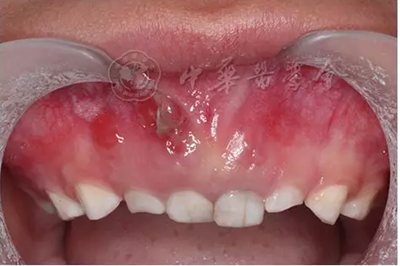

(1)疾病定義及口腔表現(xiàn):成骨不全是一種少見的先天性骨骼發(fā)育障礙性疾病,是由于Ⅰ型膠原ɑ1鏈編碼基因COL1A1和ɑ2鏈編碼基因COL1A2突變導(dǎo)致的結(jié)締組織遺傳性疾病,遺傳方式為常染色體顯性或隱性遺傳。成骨不全的臨床主要特征為多發(fā)性骨折、關(guān)節(jié)松弛、藍(lán)鞏膜、牙本質(zhì)發(fā)育不全和進(jìn)行性耳聾。根據(jù)疾病的臨床表現(xiàn)和遺傳方式分為4型,其中Ⅰ型和Ⅳ型有牙齒的表現(xiàn)?;純喝檠篮秃阊莱淑晟蛩{(lán)灰色半透明狀,釉質(zhì)正?;虬l(fā)育不全、易剝脫,牙齒磨耗明顯(圖4)?;颊呷谘例X磨損嚴(yán)重,面下1/3垂直距離降低。影像學(xué)檢查顯示牙齒冠根交界處變窄,早期牙髓腔寬大,隨著牙齒的不斷磨耗,大量繼發(fā)性牙本質(zhì)沉積,髓腔明顯縮小甚至閉鎖,根管呈細(xì)線狀,嚴(yán)重時(shí)完全消失。組織病理學(xué)檢查可見釉質(zhì)牙本質(zhì)界變平,缺少正常貝殼狀結(jié)構(gòu)。牙本質(zhì)結(jié)構(gòu)異常,牙本質(zhì)小管數(shù)目減少、排列紊亂。

圖4 5歲成骨不全癥患兒乳牙呈琥鉑色,重度磨耗

(2)治療原則:主要是增強(qiáng)骨密度、降低骨脆性以減少骨折的發(fā)生,矯正骨骼畸形??谇恢委熢谠缙趹?yīng)預(yù)防或減輕牙齒過度磨耗,可以做全牙列墊,恒牙可進(jìn)行全冠修復(fù),乳磨牙可采用不銹鋼預(yù)成冠修復(fù)。對出現(xiàn)牙髓根尖周感染的牙齒早期應(yīng)盡可能進(jìn)行根管治療,但如髓腔及根管已經(jīng)閉鎖,牙髓治療將非常困難,必要時(shí)可采用根尖手術(shù)。